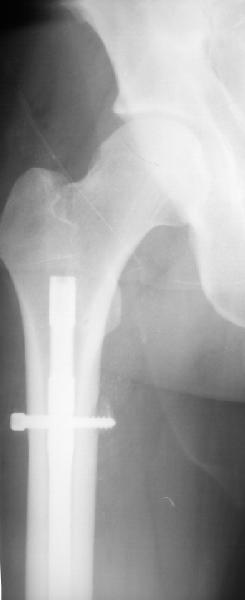

Уважаемые коллеги,пожалуйста, подумайте над следующим ребусом. В нашу клинику поступилпациент из области, 17лет, получивший травму в ДТП 25.08.04, открытый перелом бедра, при поступлении наложено скелетное вытяжение.

30.09.04 на операции выявлен вывих бедра и перелом голени на этой же стороне. Остесинтез бедра все же выполнен, и по заживлении раны пациент переведен к нам. Кроме того у пациента нейропатия седалищного нерва на этой же стороне. В нашей клинике планируется наложение аппарата таз-бедро, для постепенного низведения бедра с последующим открытым вправлением, замена фиксатора на запираемый гвоздь и блокируемый остесинтез голени. Вариант с первичным эндопротезированием мы не рассматривали из-за юного возраста пациента. Вопрос с чего начать? Кроме того, сгибание в коленном суставе в настоящее время (95 градусов) затрудняет остеосинтез голени.Стоит-ли менять гвоздь? Или же спилить торчащий конец во время открытого вправления? Может, попробовать все сделать одномоментно? Заранее спасибо.

Помните у Жванецкого-когда лежишь на спине носки ботинок куда смотрят?По снимкам трудно сказать достоверно-но по-видимому синтез сделан с ротацией.Мое мнение- вначале зафиксировать голень-интерлокинг или плата или аппарат. Потом interlocking на бедро -reposition kone4no, и после этого открытая одномоментная редукция вывиха. Все

Удаление гвоздя ( гвоздь тонкий , поэтому похоже фиксация ротационно нестабильна)

Просьба простить за длительное молчание, не было фотоаппарата, чтобы перенести рентгенограммы. Больного прооперировали в прошлый четверг, как и предполагали, голень проблем не доставила(настолько, что даже не ввели дистальные винты по ряду причин: срок после травмы, целая малоберцовая, последующая длительная ходьба без нагрузки, да и гвоздь сел плотно). Изначально планировали после удаления фиксатора антеградно завести стержень и утопить конец, но вопрос был исчерпан, когда выяснилось, что все имеющиеся стержни слишком длинные, пришлось ретроградно забить большеберцовый гвоздь, после рассверливания; серьезные проблемы возникли с устранением ротации. В вертельной области сломали стержень-джойстик(привет установщику эндопротеза), дальнейшие манипуляции проводили пучком спиц и стержнем с кондуктором. Закончили все аппаратом таз-бедро. Решили что возможные огрехи с ротацией устраним после открытого вправления. Снимки прилагаю. Спасибо за участие в обсуждении. Обязуюсь информировать о дальнейших этапах лечения.